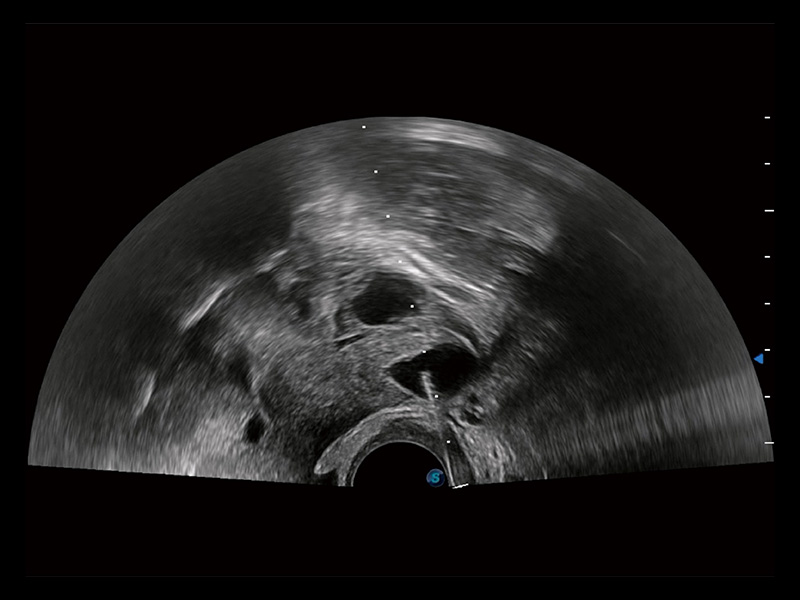

临床图

超声引导下胚胎移植

输卵管间质部妊娠